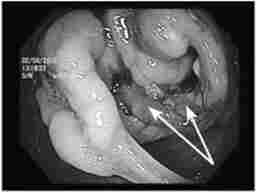

Мал. 14.6.

Фіброколоноскопія. Рак ободової кишки

Фіброколопоскопія (ФКС) - в даний час це основний метод діагностики раку ободової кишки (рис. 14.6). Фіброколопоскопія є огляд слизової оболонки товстої кишки за допомогою спеціальних гнучких ендоскопів з волоконної оптикою. З метою морфологічної верифікації пухлини під час колопоскопіі може бути виконана прицільна біопсія слизової оболонки.

Метод ФКС досить безпечний, хоча його проведення і представляє значні методичні труднощі і вимагає від ендоскопіст певної майстерності. Це пояснюється перш за все анатомічними особливостями товстої кишки, яка має цілий ряд природних вигинів і фізіологічних сфінктерів. Перед ФКС необхідно провести пальцеве дослідження прямої кишки і ректороманоскопию (детально ці методики описані в гл. 15).

Ендоскопічне дослідження з прицільною біопсією при раку товстої кишки дозволяє не тільки істотно підвищити відсоток виявлення пухлин цієї локалізації (на 20-30% в порівнянні з даними ирригоскопии), але і встановити гістологічну будову пухлини, що має значення для вибору обсягу оперативного втручання, а також визначення прогнозу захворювання.